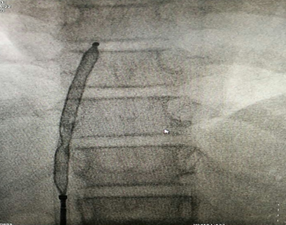

正在釋放的封堵器

在征得患者及家屬同意后,醫(yī)院心血管內(nèi)科手術(shù)團(tuán)隊(duì)在小章右側(cè)大腿根部做了局部皮膚麻醉,穿刺股靜脈成功后,經(jīng)血管插入一根幾毫米的導(dǎo)管,將封堵器送至缺損部位釋放。術(shù)后立即做心臟彩超及心電圖檢查,證實(shí)無(wú)殘余分流,無(wú)傳導(dǎo)阻滯等并發(fā)癥,手術(shù)成功。小章的先天性心臟病得到了“根治”,手術(shù)總共耗時(shí)約一個(gè)半小時(shí)。

封堵器釋放完畢